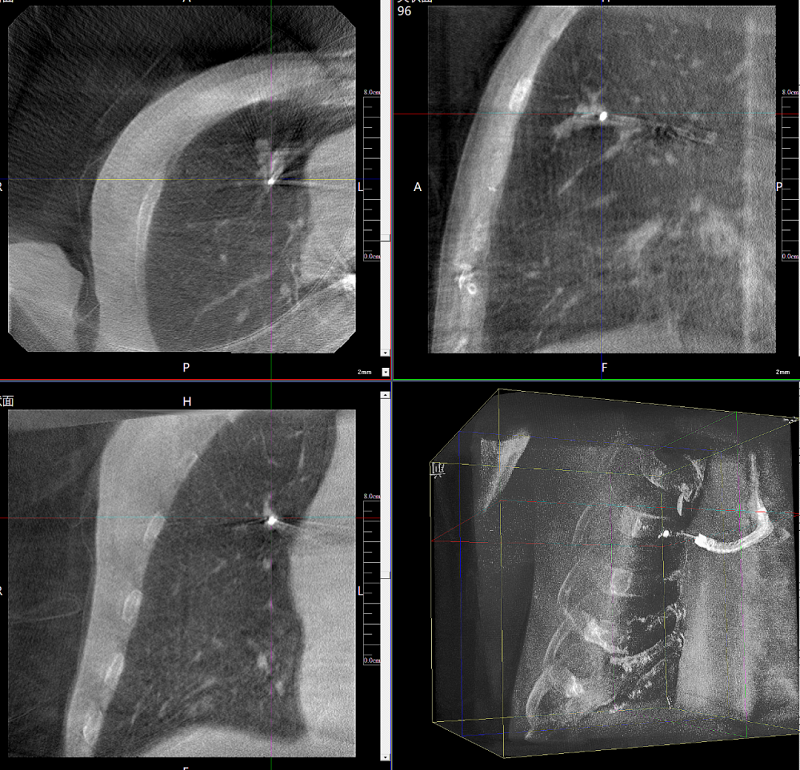

病例1:右側股骨遠端骨骺骨病(13歲)

二維影像看不到病灶點

三維切面影像可以看出病灶點